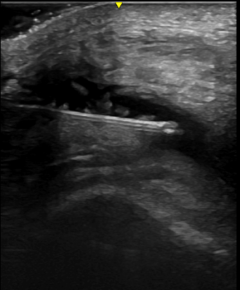

Injections have historically been performed using touch to identify physical landmarks, without the ability to confirm the accuracy of the injection. Ultrasound can be used to help providers improve the accuracy and effectiveness of injections.

During an ultrasound-guided injection, the needle can be visualized in “real time,” and adjustments can be made if needed. Ultrasound guided injections have been shown to reduce injury, have less side effects, and improve patient comfort. Both steroids and hyaluronic acid injections can be done under ultrasound guidance.

We are able to offer ultrasound guided synovial biopsy for diagnostic and research studies. US guided synovial biopsy is similar to an US guided joint injection or aspiration. The skin over the joint is cleaned with antibacterial scrubs. The skin and joint capsule is numbed with lidocaine. Ultrasound is used to guide the needle directly to the joint capsule. Fluid and/or synovial tissue can then be removed through the needle. The synovial biopsy needle is introduced with a guide. The needle and guide are slightly larger than the joint injection/aspiration needle. The guide is left in place while the biopsies are done. Four to ten biopsies can be done through the guide. Once the guide is in place, the needle does not go through the skin again.